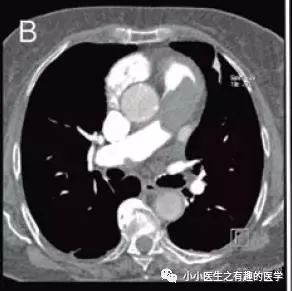

82岁女老人,劳力性呼吸困难,近期加重。

An 82-year-old woman with no previous history of heart or lung diseases presented with exertional dyspnoea and episodes of an acute shortness of breath over the preceding month.

看CT,妥妥的血栓了。

疑诊肺栓塞,抗凝治疗。

The patient was initially anticoagulated for presumed pulmonary thromboembolism.

患者血流动力学恶化,心源性休克死亡。

The patient suffered haemodynamic deterioration and died from cardiogenic shock.

为什么涅?为什么按照肺栓塞治疗,患者还是去见马克思了?偶,歪国人喜欢见上帝。

肿么办?你的灵魂去见上帝,你的肉体给我解剖学习。

病理:肺动脉内膜肉瘤。

Macroscopic (Panels G and H) and microscopic (Panel I) examination revealed the presence of an intimal sarcoma of the pulmonary artery.